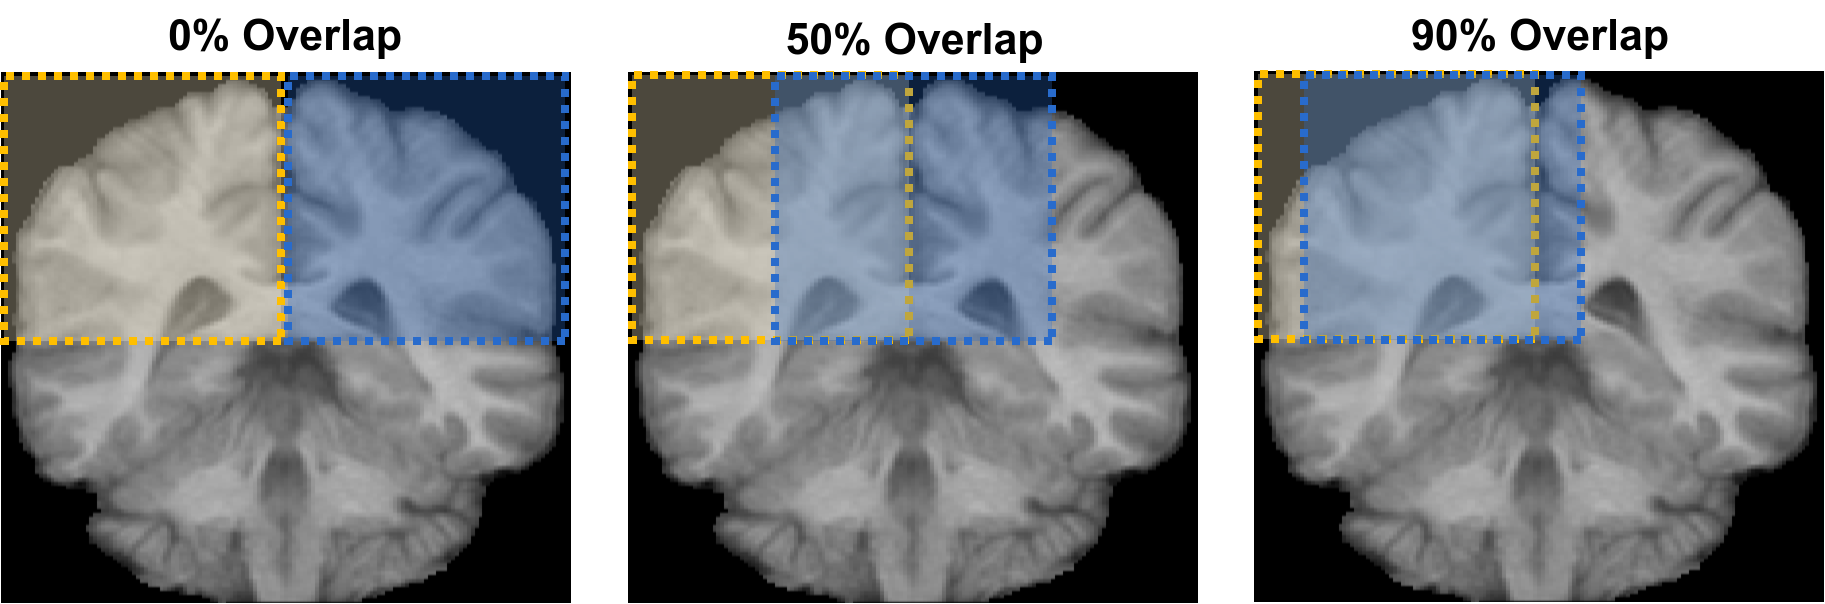

2.4.1 Overlapping sampling in training and testing

One of the drawbacks of networks performing dense-inference is that – under similar conditions – the number of parameters increases. This implies that more samples should be used in training to obtain acceptable results. The most common approach consists in augmenting the input data through transformations – e.g. translation, rotation, scaling. However, if the output dimension is not equal to the input size, other options can be considered. For instance, patches can be extracted from the input volumes with a certain extent of overlap and, thus, the same voxel would be seen several times in different neighbourhoods. An example of this technique can be observed in Fig. 2. Consequently, (i) more samples are gathered, and (ii) networks are provided with information that may improve spatial consistency as illustrated in Fig. 3 (a-d).

The sampling strategy aforementioned can be additionally enhanced by overlaying predicted patches. Unlike sophisticated post-processing techniques, the network itself is used to improve its segmentation. As depicted in Fig. 3 (e-h), the leading property of this post-processing technique is that small segmentation errors – e.g. holes and block boundary artefacts – are corrected. The consensus among outputs can be addressed through majority voting, for instance.

To evaluate the effect of extracting overlapping patches in training and testing, we run all the architectures on the three datasets contemplating three levels: null, medium and high (approximately 0%, 50% and 90%, respectively). On IBSR18 and iSeg2017, the evaluation was carried out using a leave-one-out cross-validation scheme. On MICCAI2012, the process consisted in using the given training and testing sets.

Medium level of overlap patch extraction, in both training and testing, led to improvement w.r.t. null degree cases but yielded lower values than when using a high extent of overlap. That is to say, the general trend is: the more the extent of overlap, the higher the overall performance of the method. The price to pay for using farther levels of overlap is computational time and power since the number of samples to process increases proportionally. For example, given an input volume with dimensions and a network producing output size of , the number of possible patches to be extracted following the null, medium and high overlap policies are , and , respectively.